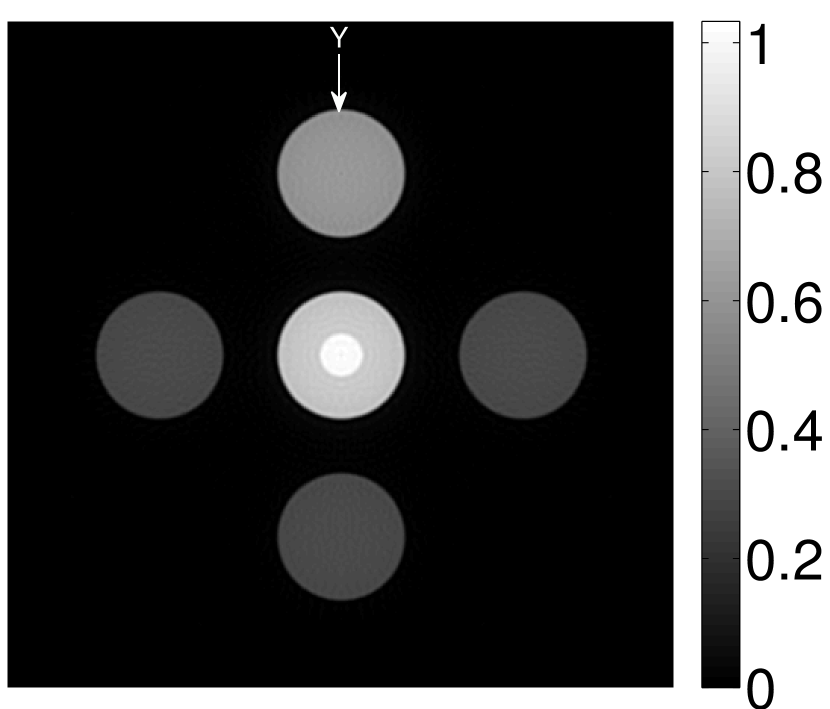

Figure 2(a) shows the image reconstructed by use of the conventional iterative method that utilized a system matrix based on EIR-2. Different values of the regularization parameter from the interval were considered. The reconstructed image with the value of that minimized the RMSE was chosen to represent the best performance of the conventional iterative method. Figure 2(a) and the profile in Figure 2(c) demonstrate that the use of an inaccurate EIR can result in strong artifacts and distortions in images reconstructed by use of the conventional methods.

When the VP algorithm was applied, different values of the regularization parameter from the interval and from the interval were considered. The image that minimized the RMSE was chosen and displayed in Figure 2(b). As revealed by this image and the profiles in 2(c), the VP algorithm yielded an image with fewer artifacts and distortions, and image fidelity was improved as reflected by the reduced RMSE.

Figure 7(a) reveals that use of the inaccurate EIR in the conventional iterative method created strong artifacts and distortions. Figures 7(b) confirms that the artifacts and distortions were significantly mitigated when the VP method was employed. Image profiles for both cases are shown in Figures 7(c). The overall accuracy of the recovered EIR, shown in Figure 7(d) and 7(e), was improved, but it contained spurious oscillations.